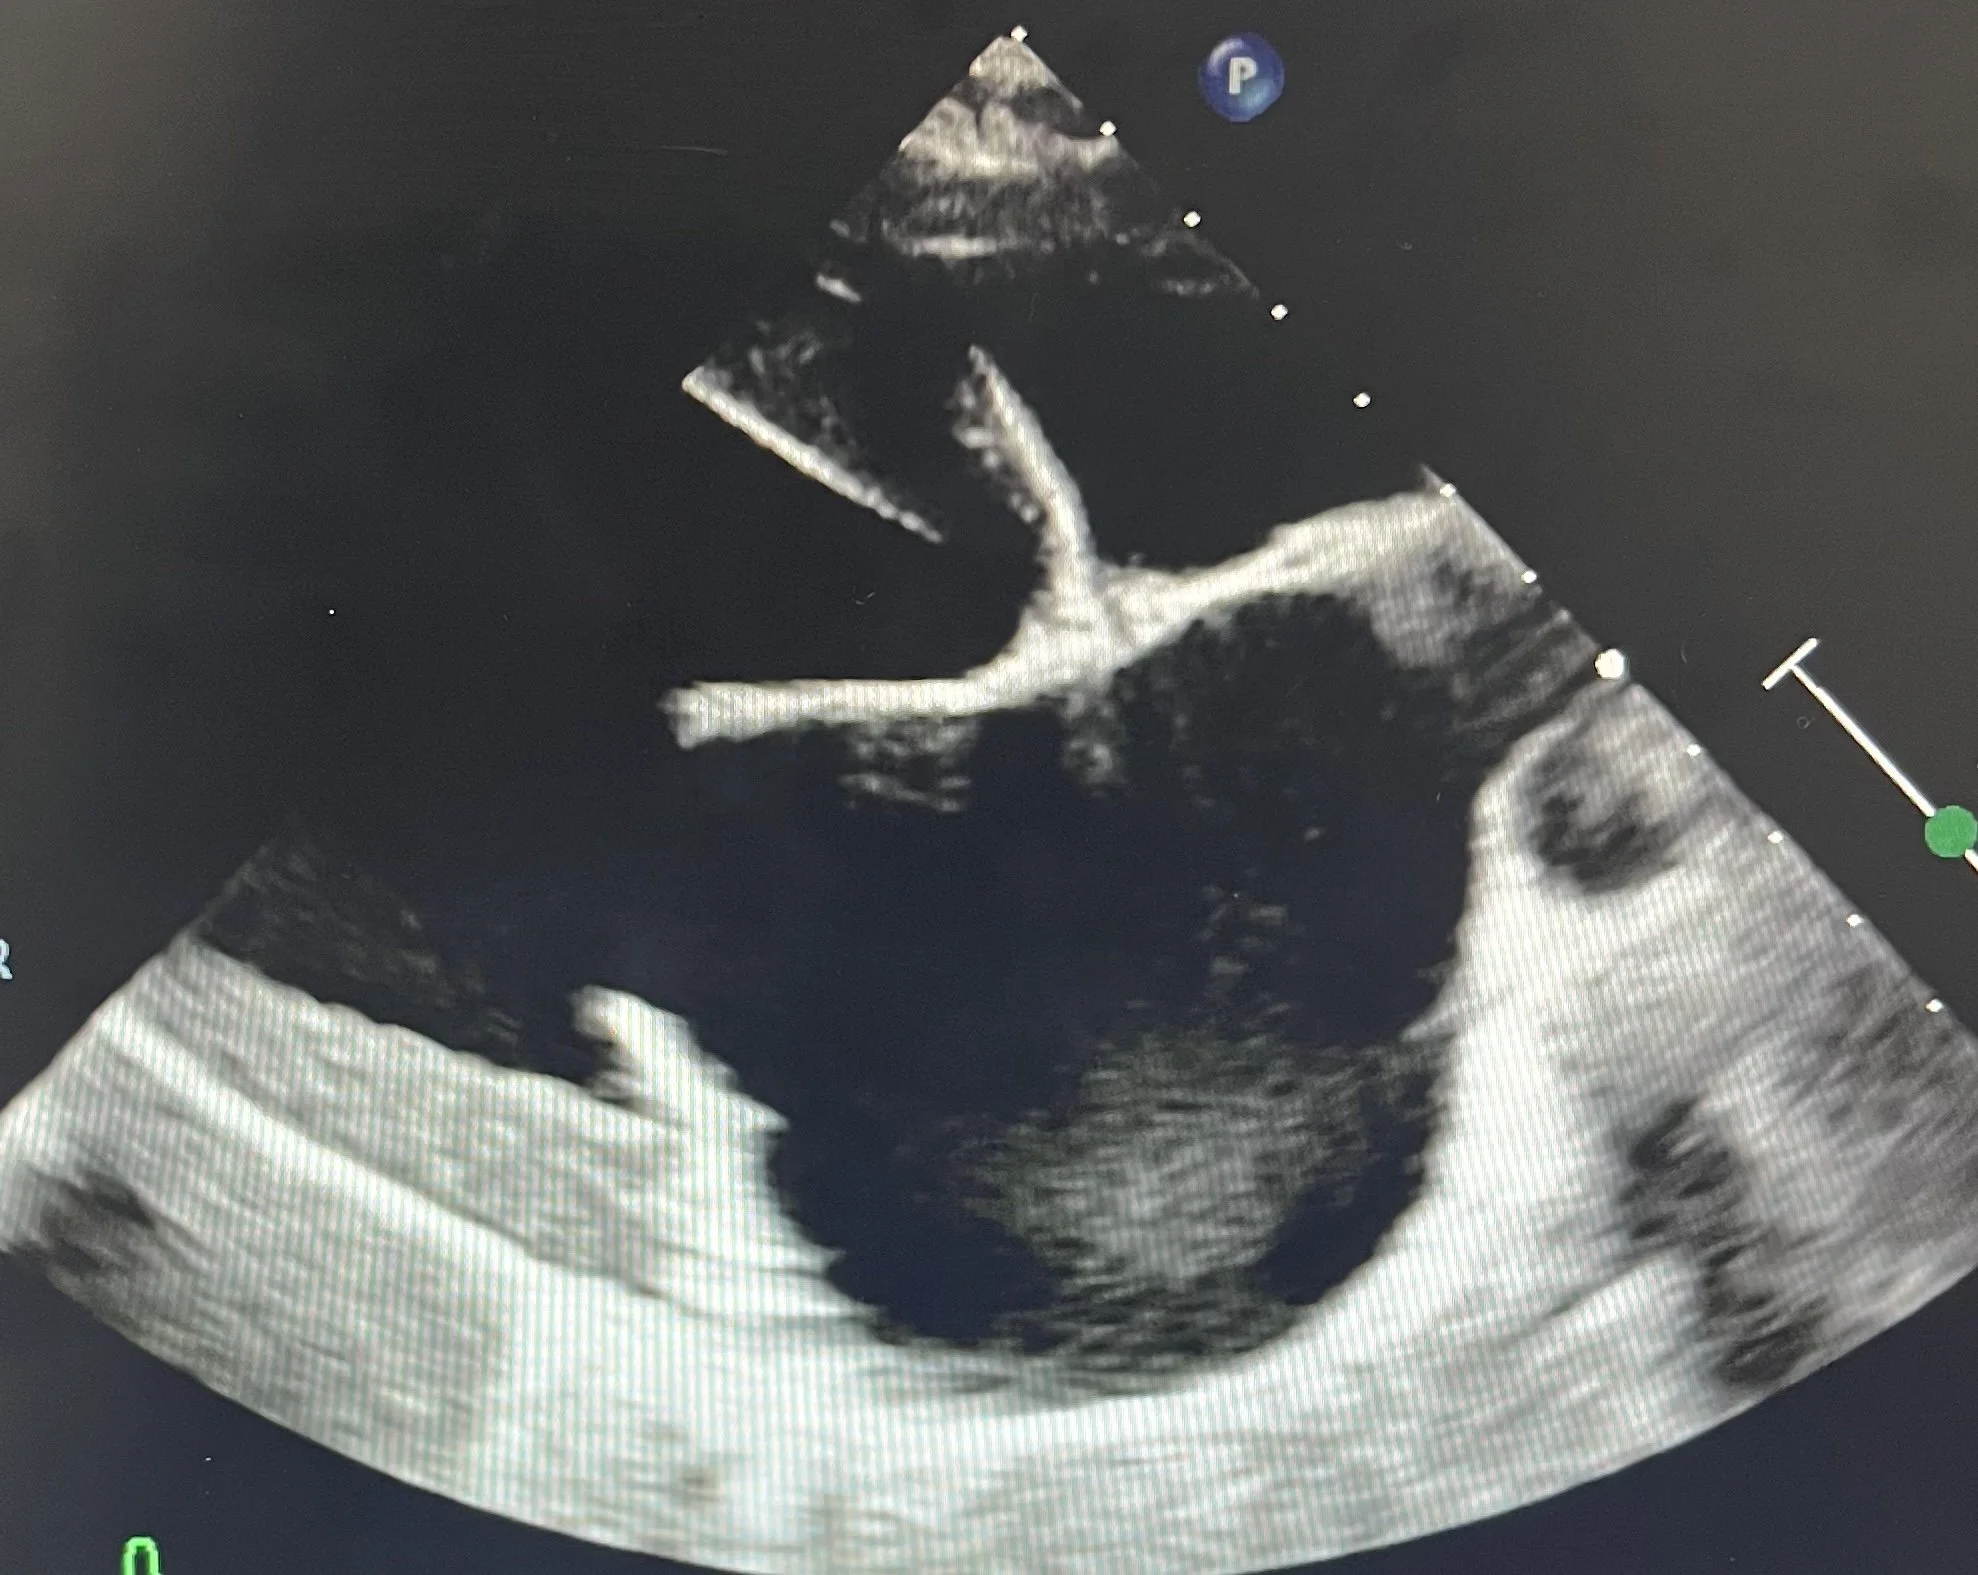

Echocardiography

An echocardiogram (ultrasound of the heart) is a diagnostic tool that is used when your pet is diagnosed with a heart murmur. A heart murmur is caused by turbulent blood flow that we can hear with our stethoscope. A heart murmur can often be due to underlying disease. An echocardiogram can allow a definitive diagnosis for your pet.